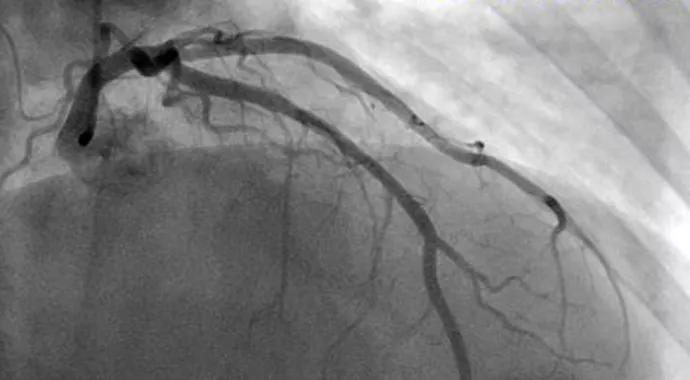

When catheterization reveals normal coronary arteries in a patient complaining of angina, the tendency is to suspect a noncardiac condition. But if the patient continues to have angina, the diagnosis of coronary artery (CA) spasm should be considered.

Provocative ergonomine testing is conducted in the cath lab. We first image the coronaries to ensure they are free of obstructive CAD. A bolus of ergonovine is then injected intravenously. Most patients will respond within 5 minutes. We take a complete EKG every minute, as changes in the EKG sometimes appear prior to angina. As soon as angina occurs, we reimage the coronaries. The patient is then given a syringe of premixed nitroglycerine or verapamil to reverse the spasm. The EKG should immediately normalize.